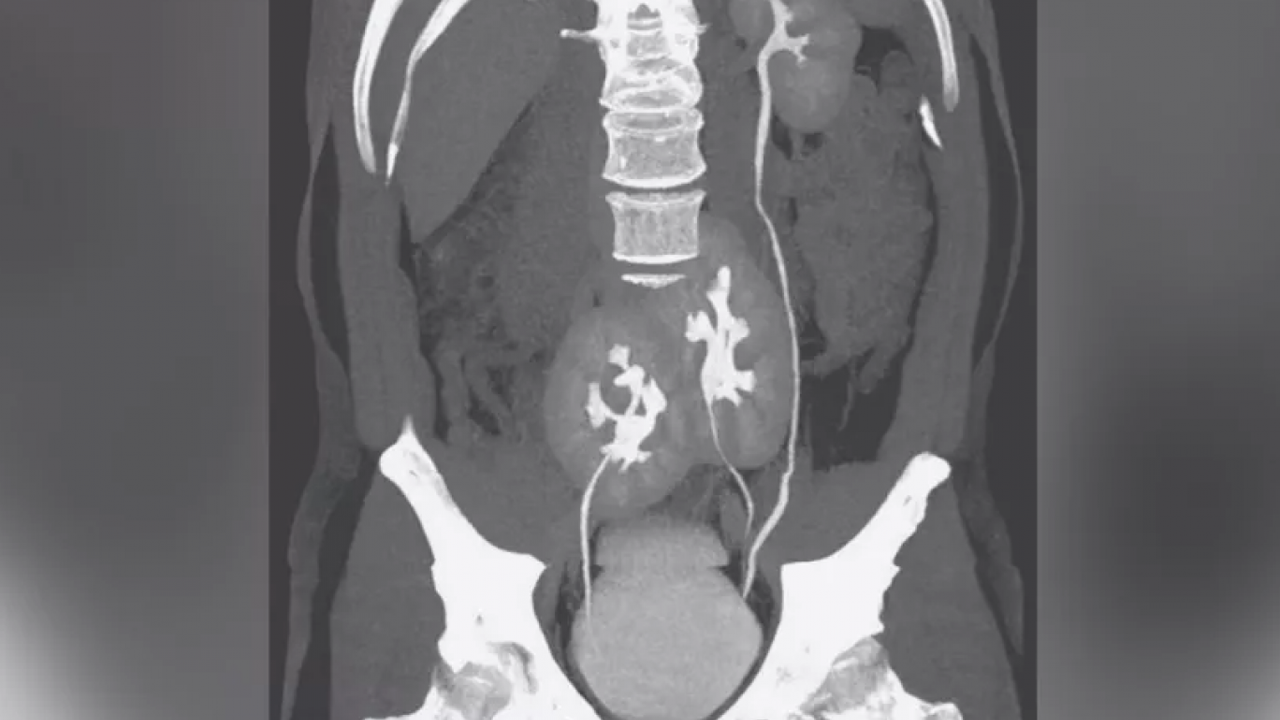

İHA’nın haberine göre; Balıkesir''de oturan ve çocuk yaşta kronik böbrek yetmezliği teşhisi konulan 36 yaşındaki Cafer Gürbüz, 2002 yılında Ege Üniversitesi Hastanesinde nakil operasyonu geçirdikten sonra 3 böbrekle yaşamına devam etti.

Bu böbreğinin de işlevini yitirmesinin ardından 2019''da 2 yaşındaki bir bebeğin böbrekleriyle Bursa Uludağ Üniversitesi Tıp Fakültesi Hastanesinde yeniden nakil olan Gürbüz, ikisi sağlıklı 5 böbrekle hayatını devam ettirdi.

İdrar yolu enfeksiyonu nedeniyle tekrar üniversite hastanesinde tedaviye alınan hastanın, yeni böbreklerinin zarar görmemesi için doğuştan itibaren kendisinde olan iki böbreği alındı.

3 böbrekle yaşamını devam ettiren Gürbüz, yeniden sağlığına kavuşmanın mutluluğunu yaşıyor.